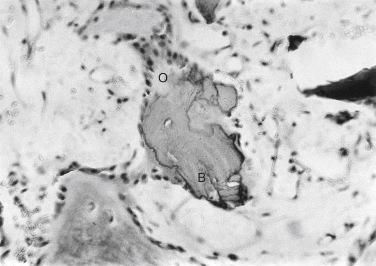

The ready availability and clinical success of morselized allograft has led to its increasing use for reconstruction of bone defects. Over the years, a considerable body of knowledge has been produced to define how this material functions. Granulated allograft bone comprising pieces smaller than 0.5 cm often is resorbed and removed by the inflammatory process. Bone pieces that are between 0.5 and 1 cm in diameter are the most effective because they resist resorption and allow rapid vascularization. Larger segments are much more difficult to construct and fit to the defect, and they are slower to ossify and incorporate. Rapid healing and ossification occurs routinely when morselized bone grafting is done with appropriate technique, provided that the implants are stable and the allograft is surrounded by viable bone ( Figs. 22A.4 to 22A.7 ). Although morselized cancellous allograft is osteoconductive rather than osteoinductive, it serves as an effective scaffolding for new bone formation. Demineralized bone added to the morselized allograft provides the osteoinductive stimulus and probably augments healing of failed massive implants in which large defects are encountered. The technique used with morselized allograft is important to the rate and completeness of healing in large defects. Loose (rather than tight) packing improves vascularization and hastens bone formation. Addition of osteoinductive proteins encourages bone formation deep in the graft. Implantation that encourages early load bearing improves bone formation and maturation.

FIGURE 22A.4, Photograph of a histologic section from a 3-week postoperative biopsy specimen. Granules of demineralized bone (B) are visible and are surrounded by plump osteoblasts (O) and new osteoid. Vascular stroma is present throughout the allografted area. No histologic evidence of bone resorption is seen (hematoxylin-eosin stain; original magnification ×160).